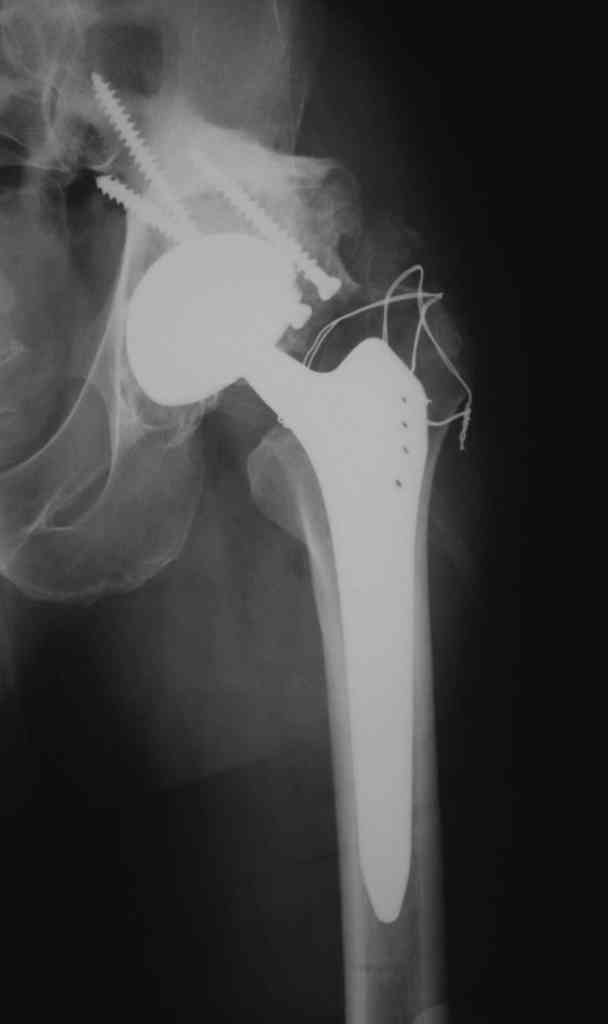

Еще одно наблюдение, неправильно сросшийся перелом заднего отдела ВВ с ввихом головки бедра 16-и летней давности.

С уважением, Р.Тихилов

Большое спасибо за ответ, примеры впечатляют, особенно случай с переломом задней колонны. Интересно отличаются ли у Вас доступ при значительных проблемах в задних отделах от стандартного, всегда ли хватает головки или берете кость из других мест, отличается ли послеоперационное ведение у таких больных (когда нагрузка?).